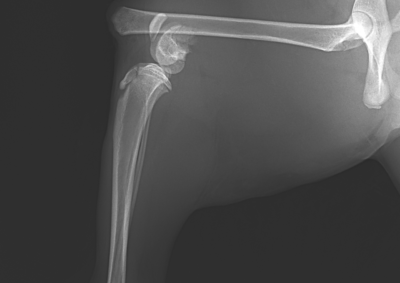

注意 ボタンをクリックした先に、治療中および手術中の画像が説明で使用されている場合がございます。 そのような画像に弱い方は閲覧なさらないようお願いいたします。 整形外科 若齢犬の橈骨固定術 #271 整形外科 前十字靭帯断裂(中型犬)に対するCBLO #255 整形外科 超小型犬に対する上腕骨遠位Y字骨折 整形外科 大型犬の前十字靭帯疾患(慢性経過)に対するCBLO #254 整形外科 橈骨固定術 #270 整形外科 膝蓋骨内方脱臼に対する人工滑車置換術 PGR #23 整形外科 犬の前十字靭帯(疾患)部分断裂に対するCBLO #253 整形外科 犬の前十字靭帯断裂に対するCBLO #252 整形外科 膝蓋骨内方脱臼+前十字靭帯断裂に対するPGR#22・LSS 整形外科 大腿骨骨折 整形外科 橈骨固定術 #269 整形外科 上腕骨外顆骨折の癒合不全 123456> 症例カテゴリー 放射線治療整形外科軟部組織外科脳神経外科内科腫瘍外科救急・集中治療リハビリテーション科腫瘍内科内視鏡科脳神経科呼吸器外科中医・漢方猫の腎移植循環器科